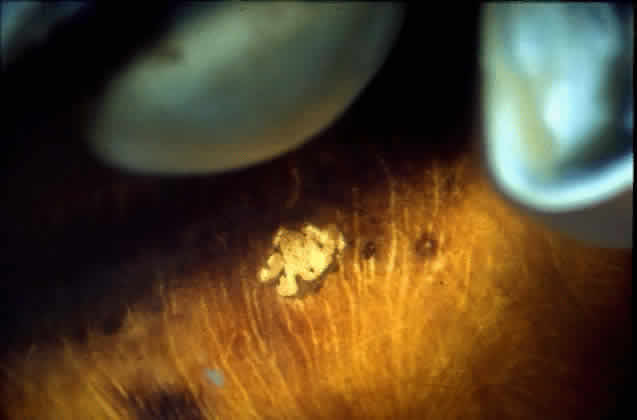

Fig. 32. Area of peripheral choroidal ischemia in gross specimen.

Fig. 33. Photomicrograph of area corresponding to that in Figure 31 shows ischemic atrophy of outer retina and retinal pigment epithelium. (H & E, × 25)